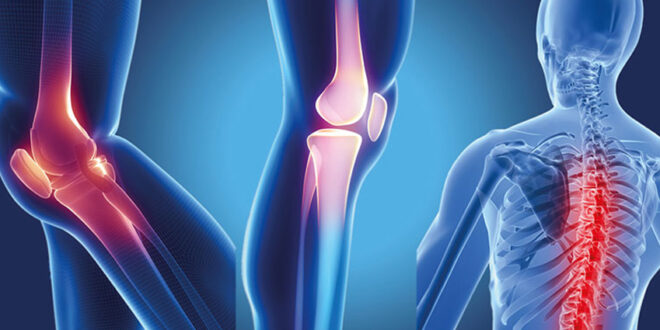

Bone and joint issues are becoming more common because of busy lifestyles, injuries, aging, and conditions like arthritis. When pain starts to interfere with your daily life, it’s important to get care from a skilled orthopedic doctor. If you need a top bone specialist in Mumbai, Dr. Kunal Patel is a leading name known for deep diagnosis, precise treatment, and successful recovery.

Conditions Treated by Dr. Kunal Patel

When looking for a reliable bone specialist in Mumbai, it’s important to find someone who can manage various orthopedic conditions. Dr. Patel specializes in:

✔ Knee Pain and Osteoarthritis

✔ Hip Joint Problems

✔ Sports Injuries & Ligament Tears

✔ Bone Fractures

✔ Spine Disorders